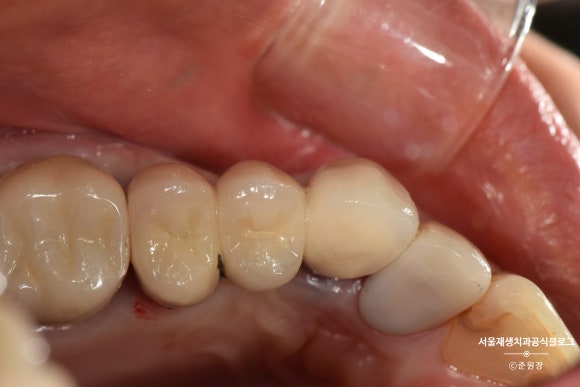

충분한 높이가 확보되었는지 확인하기 위한 치주탐침검사입니다. 눈금이 있어서 '자'처럼 쓸 수 있는 유용한 도구입니다^^

크라운을 씌우기 위해서는 최소 2~3mm의 높이가 필요합니다.

잇몸에 콕 박혀있던 요 녀석을

위 사진처럼 약~간 들어올린 상태로 고정시켰습니다.

치아가 살~짝 빠져있는 상태겠죠?

흔들리지 않겠냐고요?

약간의 생리적인 움직임만을 허용할 수 있는

레진-와이어 스플린팅을 시행합니다.

투명하고 낭창낭창한 플라스틱 와이어나 얇은 스텐와이어면 충분합니다.

인접치에 튼튼하게 고정되었습니다.

이 상태로 2주 기다려봅니다.

2주 후

연세가 조금 있으셨음에도 불구하고,

2주 후에 다행히 치아가 뼈에 단단히 결합된 상태로 재내원하셨습니다.

와이어를 제거했습니다.

최소한의 길이가 확보되긴 했지만 아직 크라운을 씌울 정도의 충분한 부피는 아닙니다.

나머지는 포스트와 레진의 도움을 받아 쌓아올립니다.